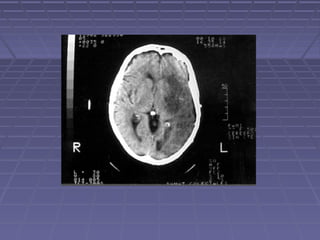

 TAC de cráneoTAC de cráneo si: persisten o aumentan lassi: persisten o aumentan las

manifestaciones clínicas, se sospechamanifestaciones clínicas, se sospecha

herniación, persiste la fiebre.herniación, persiste la fiebre.

 TC: hidrocefalia, lesiones vasculares,TC: hidrocefalia, lesiones vasculares,

tuberculomastuberculomas